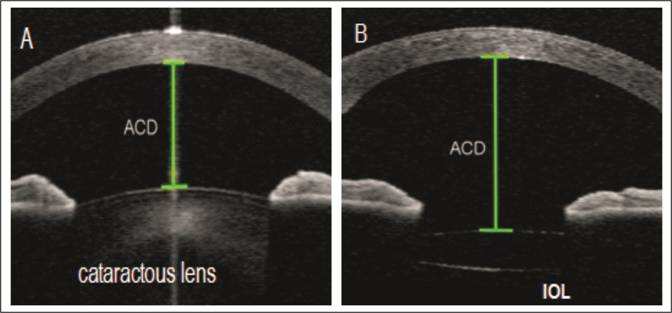

Fig. 1: Anterior

chamber angle (ACA) is the

angle between the iris anterior surface and that of the posterior corneal

surface with its apex in the angle recess. Trabecular

Iris angle (TIA) is the angle that is measured with its apex in the scleral

spur and the arms500 µm from the scleral spur passing through a point on the

trabecular meshwork and a perpendicular point on the iris.

ACA, TIA, AOD-500,

AOD-750, TISA-500, TISA-750 which are being discussed in following paragraph

along with diagrammatic illustrations.

Fig 2: Angle

opening distance at 500μm

(AOD-500) and 750μm

(AOD-750) is the distance from the corneal endothelium to the anterior surface of iris

just perpendicular to a line drawn along the trabecular meshwork at 500 and

750µm from scleral spur. Trabecular-iris

space areas (TISA) defined as the areas bounded by the corneal endothelium,

trabecular meshwork, and anterior iris surface out to a distance of 500 µm or

750 µm from the scleral spur.

In this study, we included Trabecular iris

angle (TIA) and Angle opening distance at 500μm

(AOD500). Both of these actually specify ACA depth and width and are

standardized as well. Reason not to include ACA is that it was difficult to

identify proper angle recess in many patients and thus it can lead to reduced

study sensitivity. It is important to note that ACA depth is different from

Anterior chamber depth (ACD) and this study doesn’t include ACD that is the

distance from corneal endothelium at the center of cornea to the anterior

surface of lens12. Though previous studies included ACD change that

can be well explained on this fact that thick cataractous lens is replaced with

a thin intra-ocular lens that will ultimately deepen the AC13. Another

limitation for this parameter is that it includes some portion of posterior

chamber when measured in eyes with intra-ocular lens while we are only

concerned about anterior chamber.

Fig 3: A) ACD with thick cataractous lens.

B) ACD with thin IOL. Note that little part of post. Chamber is

also included in ACD measurement when IOL is present.